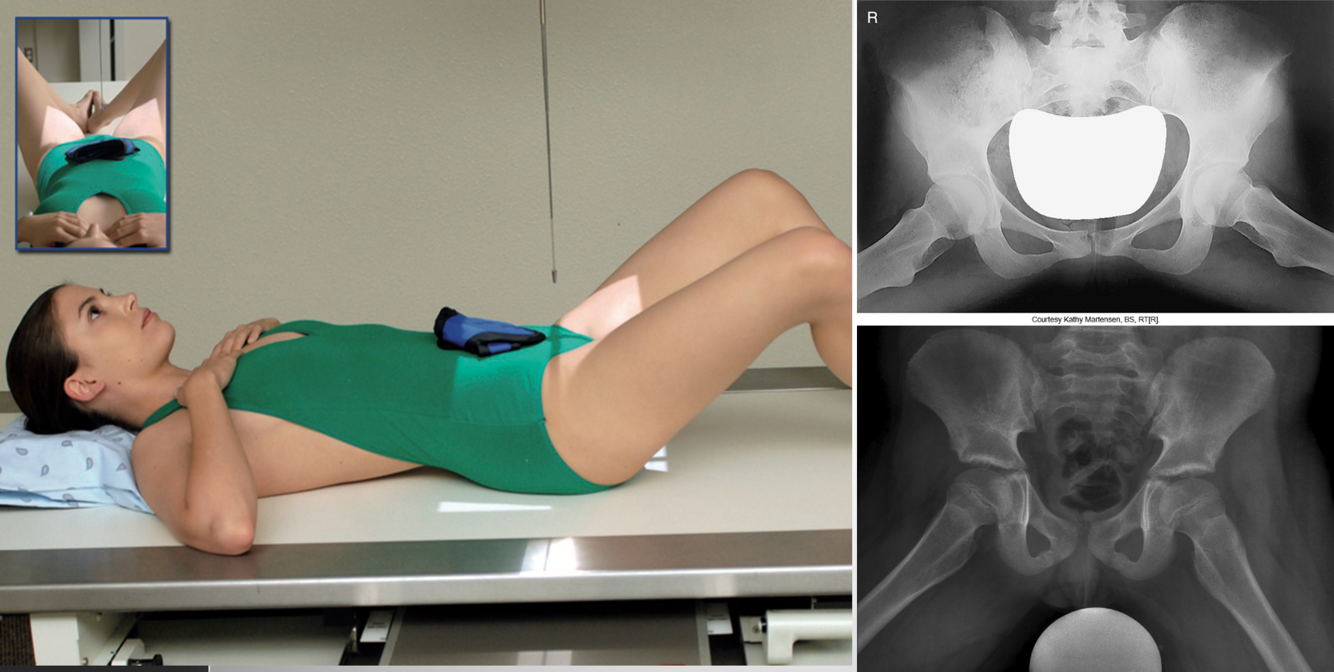

AP Pelvis

• IR 14x17 landscape. Minimum 40 SID (can use more distance for a larger pelvis to project divergent rays & decrease magnification)

• Pt supine, arms by side or on chest, can be done upright to evaluate joint spaces. Align MSP of pt to center of bucky/IR. Ensure pelvis is not rotated (ASIS equal). Separate legs and feet, internally rotate WHOLE LOWER EXTREMITY 15-20º. Use support devise if patient can’t hold position (tape/sandbags). Suspend respiration

• CR perpendicular to IR directed midway between between the level of ASIS & pubic symphysis (2” below ASIS). Ensure top of crest is in light field. Collimate to 4 sides of anatomy